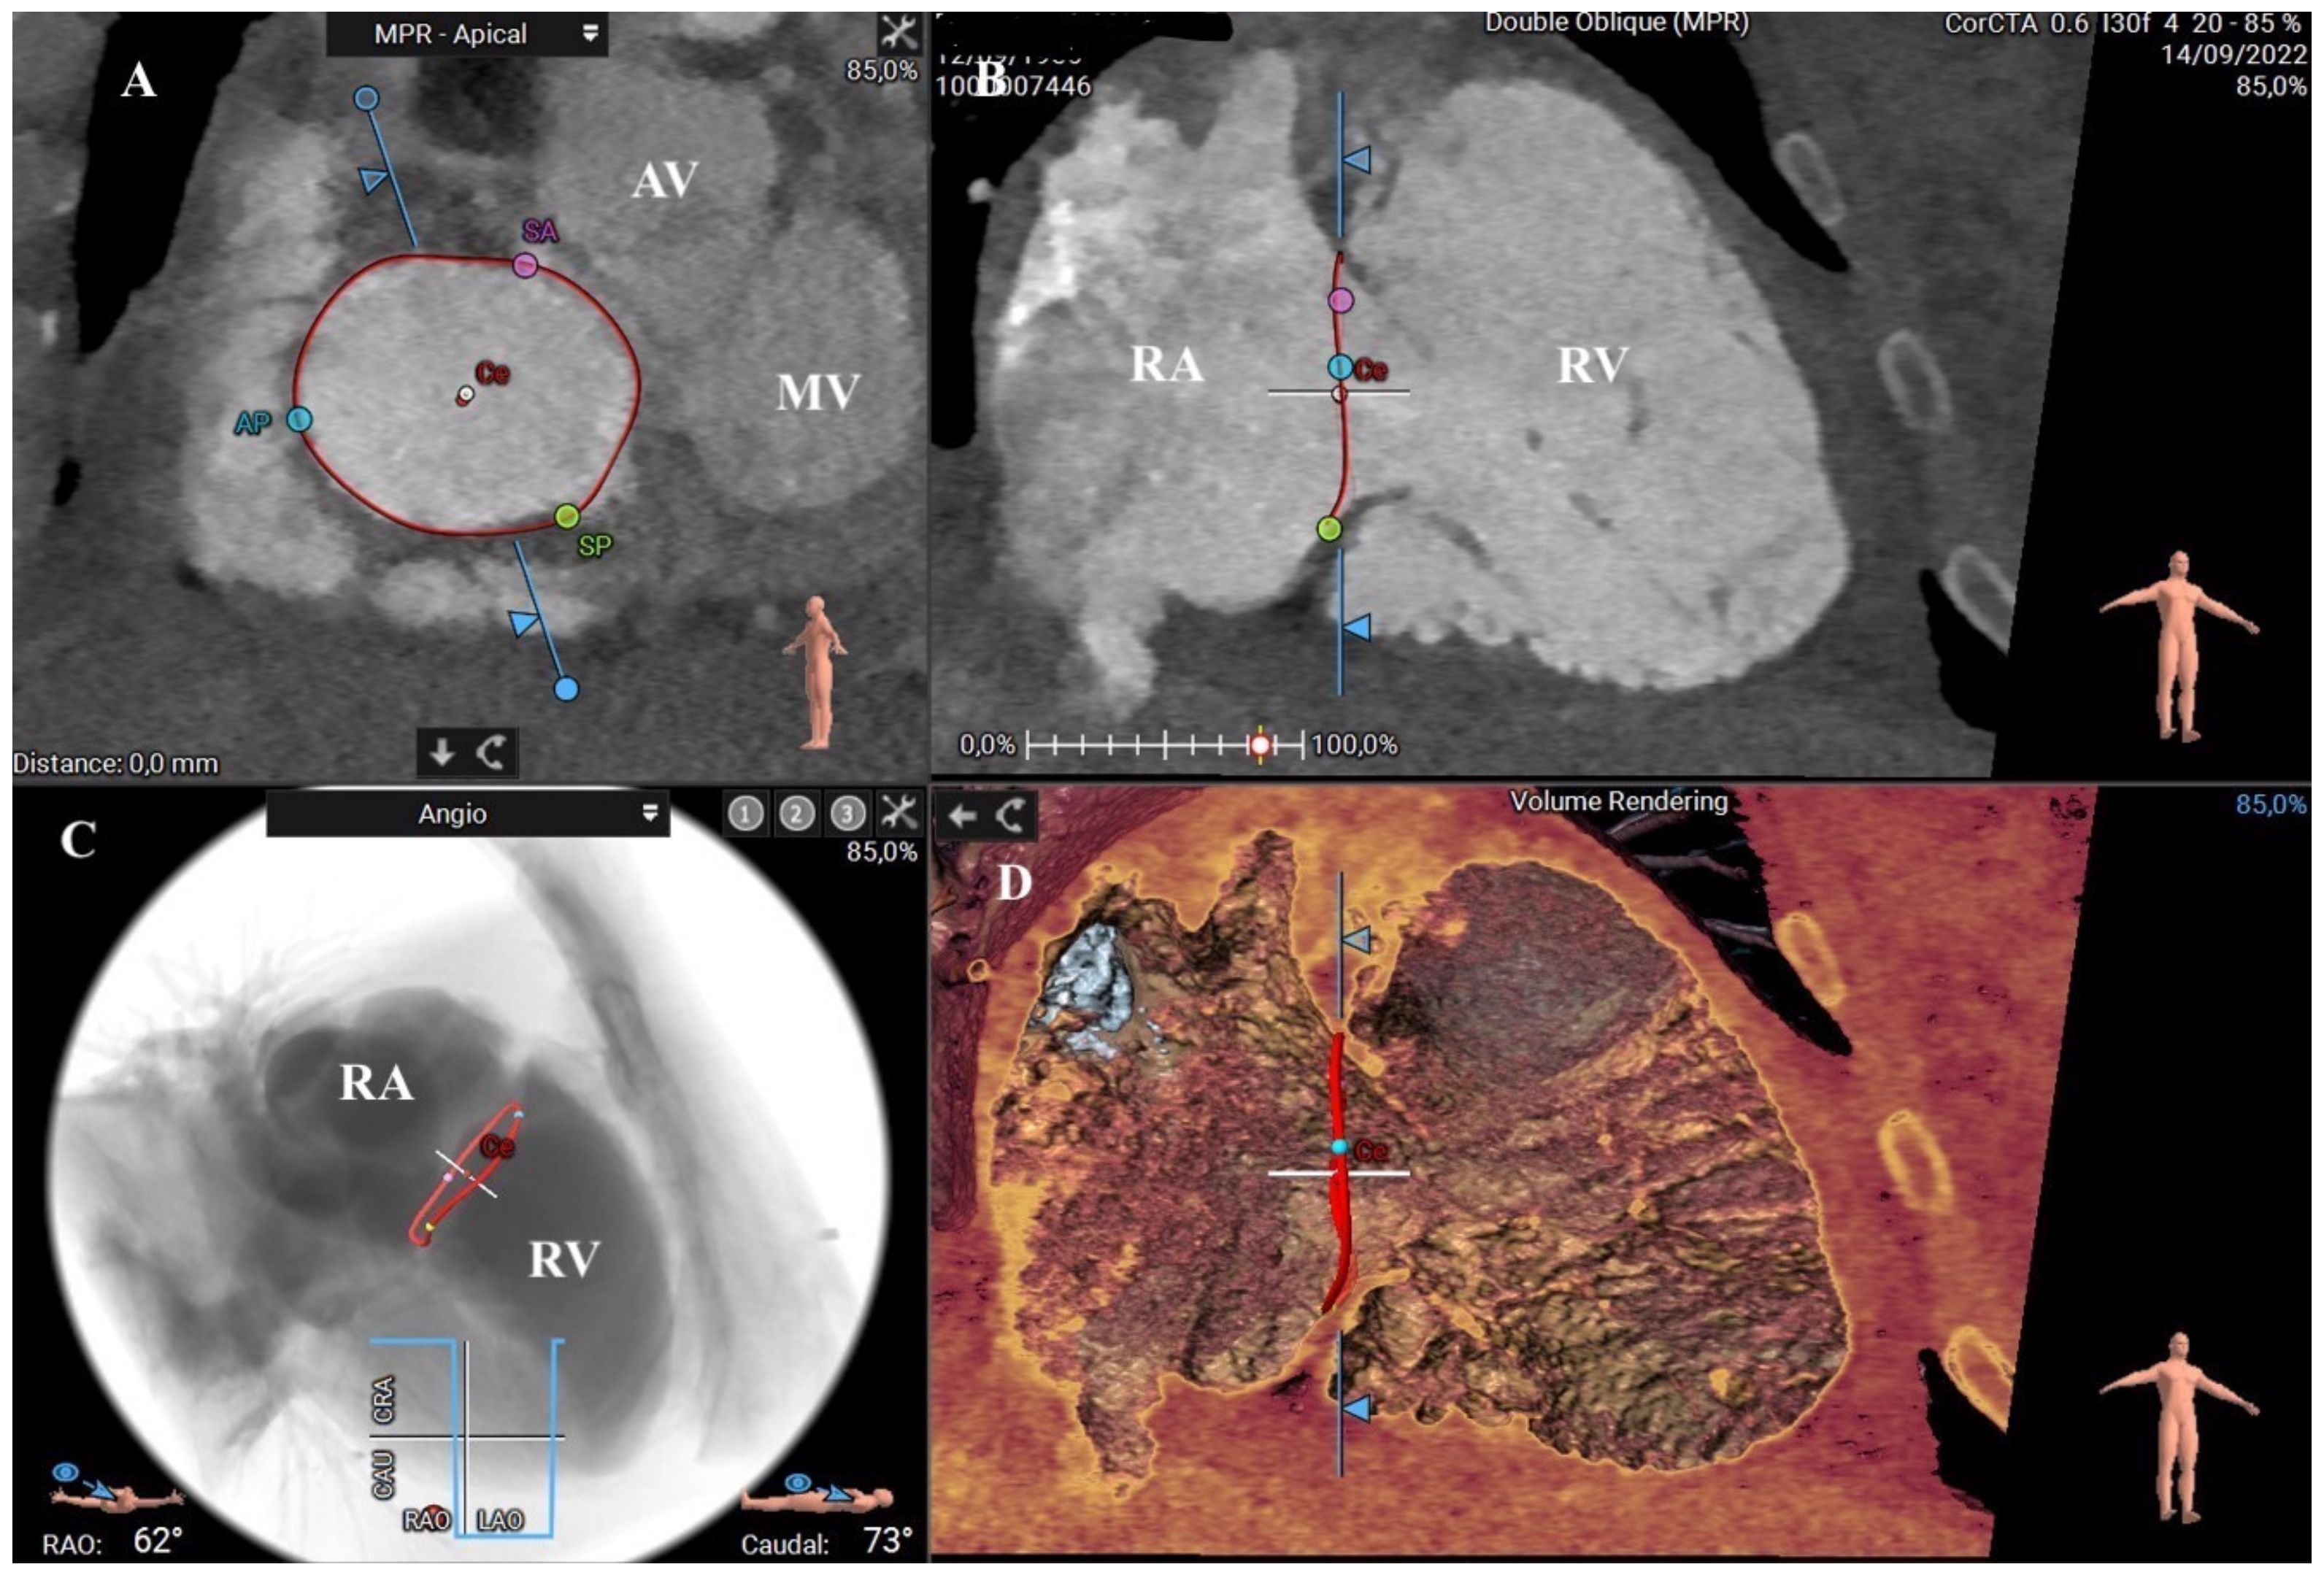

4.3. CT Assessment of the Tricuspid Apparatus for Transcatheter Procedures

The multiphasic, contrast-enhanced, retrospective cardiac-gated CT acquisition enables multiplanar reconstruction of the entire heart silhouette, including the proximal main vessels, allowing a comprehensive understanding of the right heart anatomy (Figure 11) [105].

Figure 11.

CT assessment of the tricuspid annulus using a semiautomated software-based approach (3mensio Structural Heart; Pie Medical Imaging, Maastricht, The Netherlands): (A) Transverse plane (short-axis) at level of tricuspid annulus that is delineated by the red line. The centroid of the tricuspid valve (Ce) and the three main commissures (SA: septal anterior, SP: septal posterior, AP: anteroposterior) are identified according to specific anatomical landmarks. (B) Coronal plane (long axis) at level of the anteroposterior diameter of the tricuspid annulus. (C) Fluoroscopic and angiographic simulation showing the three-dimensional position of the tricuspid annulus and commissures within the right heart chambers. (D) Three-dimensional recontraction by the volume rendering of the right chambers showing the geometrical spatial relationship of the tricuspid annulus and surrounding structures. RA: right atrium; RV: right ventricle; MV: mitral valve; AV: aortic valve.

The amounts of contrast and radiation required have been considerably reduced with the new CT scanners, as well as the duration of the acquisition phase. It is also possible to perform more precise reconstructions even in elevated heart rates, such as atrial fibrillation, a widespread pathology in patients with significant TR [106]. Notably, a dedicated protocol for tricuspid valve CT acquisition is necessary; it requires opacification of the right heart cavities by a monophasic or biphasic injection with a mixture of saline and contrast in different percentages and following bolus tracking in the right ventricle or the pulmonary artery [107].

The comprehensive assessment of the right heart and the adjacent anatomical structures, which the tricuspid defect could significantly remodel, provides an appropriate evaluation for TR severity, patients’ clinical risk stratification, anatomical suitability for tricuspid interventions, and preprocedural planning in patients undergoing TV therapies [105]. Specifically, several fundamental parameters might be obtained by CT imaging in order to design the optimal procedure and achieve the highest success rate during transcatheter tricuspid valve interventions (TTVI), such as dimensions and morphology of the TV annulus, location of commissures, tethering parameters, anatomical regurgitant orifice area, right atrium (RA) and RV dimensions, surrounding structures, device landing zone, and vascular access routes [11]. Using multiplanar reconstruction, tricuspid cross-sectional area, perimeter, septolateral (SL), and anteroposterior (AP) diameters can be obtained by a short-axis view on the annular level. The SL diameter refers to the maximal distance in septal to the lateral direction (that corresponds to the anulus measurement in the four-chamber view at the transthoracic echocardiography), whereas the AP diameter is orthogonal to the previous one. Due to the complex saddle-shaped structure of the tricuspid annulus, a 2D approach does not precisely address the valvular anatomy. Therefore, 3D semiautomated software can help in this setting [108]. Moreover, dimensions are usually obtained both at end-systole and mid-diastole because of the dynamic variability in annular size. Interestingly, in a study by Praz et al., there was a good correspondence between TEE and CT for tricuspid annulus sizing and valve area in patients with severe TR [109]. Finally, distances between commissures (anteroseptal, posteroseptal, and anteroposterior) and distances between the centrum of the TV and commissures can also be measured [12].